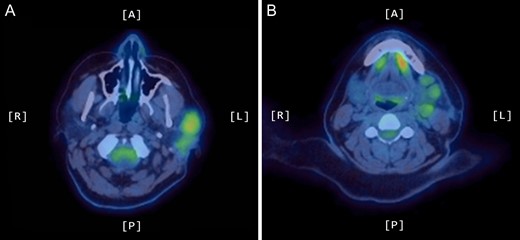

A positron emission tomography (PET) scan was subsequently arranged, which demonstrated increased uptake of the left parotid gland and several enlarged lymph nodes in the neck bilaterally (Figs 1 and 2).

Coronal PET scan showing increased uptake of the left parotid gland and enlarged left-sided lymph nodes in the neck.